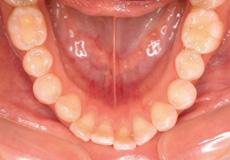

前歯のデコボコが気になる → 叢生を伴う過蓋咬合

下顎に比べ上顎が前方にずれ、上顎前突の状態であり上の前歯が下の前歯

におおいかぶさっている過蓋咬合の状態でした。

また歯のデコボコもある事から上顎の左右第一小臼歯(計2本)を抜歯して治療を行いました。

下顎のデコボコは非抜歯で改善可能と考え、抜歯していません。